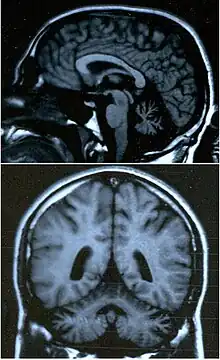

Le cervelet est le centre de la coordination fine des mouvements des muscles, l'information qui en émerge est véhiculée jusqu'aux muscles par la moelle épinière et les nerfs périphériques. Pour cette raison, une atteinte soit de la moelle épinière soit des nerfs périphériques peut causer une ataxie.